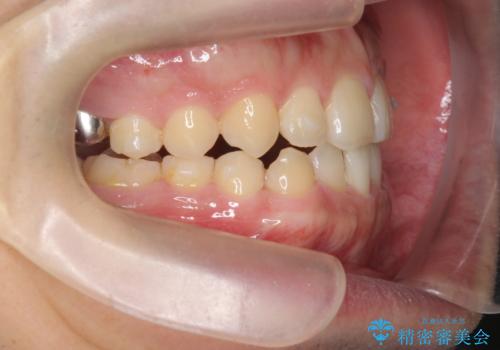

- 前歯の噛み合わせが反対になっていること、前歯の見た目の改善を希望され来院されました。

詳細な矯正検査の結果、顎の歪みが見られたため大きく歯を動かす治療ではなく前歯を主に並べることで前歯の前後関係を改善していきます。

前歯を主に動かす部分矯正であることからマウスピース矯正インビザラインによる治療を計画します。